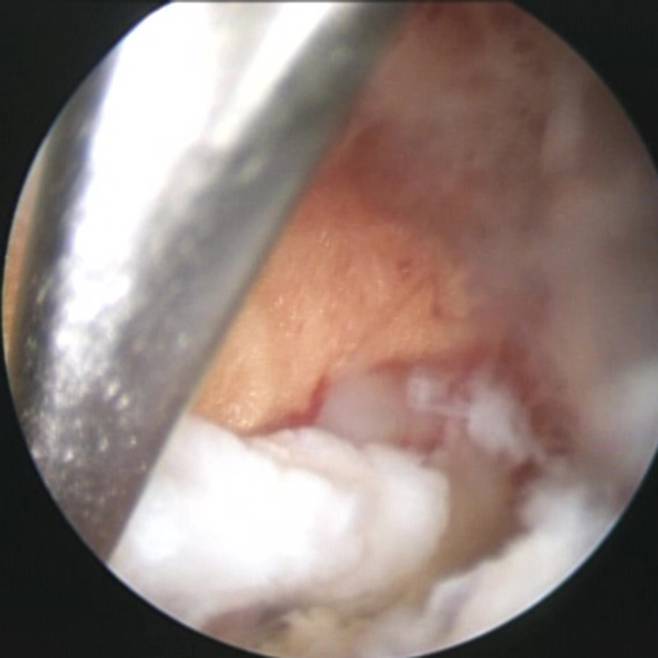

현재 표준 수술법은 요추 부위 근육을 약 30~40mm 절개하고 수술용 현미경으로 확인하면서 누출된 수핵을 제거하는 방식인 ‘현미경 디스크 절제술(Microscopic Discectomy·MD)’이다. 예전 개방수술법보다 회복이 빠르고 통증도 적지만, 근육을 벌리는 과정에서 손상과 흉터, 그리고 통증이 불가피하다는 한계가 있었다. 반면 BED는 요추 부위 두 곳을 10~20㎜ 절개한 다음 체내로 내시경 카메라를 넣고 환부를 직접 확인하면서 수핵을 제거한다.